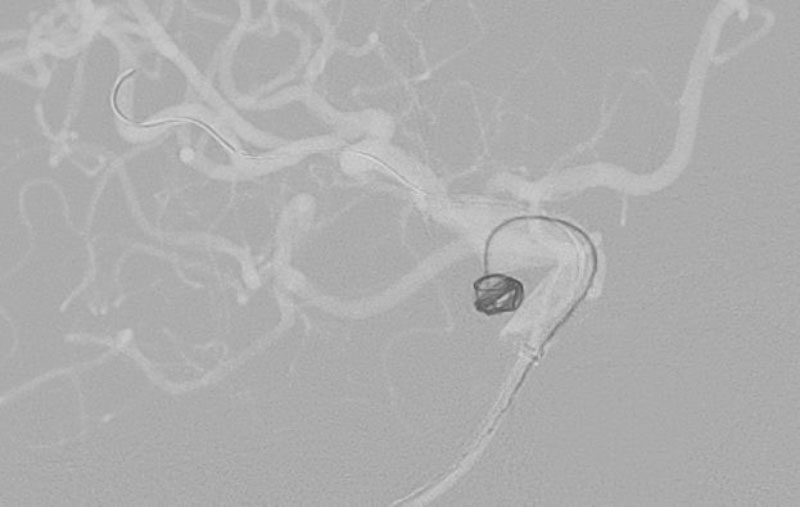

No.1628 手術中

No.1628 手術後